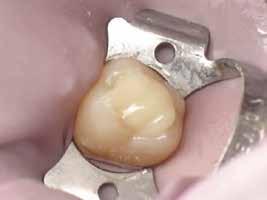

MTA-val (Mineral Trioxide Aggregate; Harvard Dental) töltöttük fel. A léziótól koronális irányban elhelyezkedő gyökércsatorna-szakaszt meleg guttaperchával zártuk, majd az MTA-val kitöltött üregre egy kis darab kollagénszivacsot helyeztünk és a lebenyt varratok segítségével eredeti pozíciójában rögzítettük (12. a–b; 13. a–b. ábra). A fog koronai részét Gradia kompozit tömőanyaggal állítottuk helyre (GC; 14. a–b; 15. ábra). Kontrollvizsgálatra két (16. a–b ábra) és négy évvel (17. a–b ábra) később került sor. A kontrollfelvételeken a bukkális kortikális jelenléte volt észlelhető. A fog körüli parodoncium egészséges volt, valamint a páciens sem számolt be tünetekről.

13. a–c ábra: A reszorbtív üreg bioanyaggal való feltöltése és a kollagénszivacs elhelyezése. – 14. a–b ábra: Posztoperatív röntgen (a), a varratok behelyezését követően látható klinikai helyzet (b).